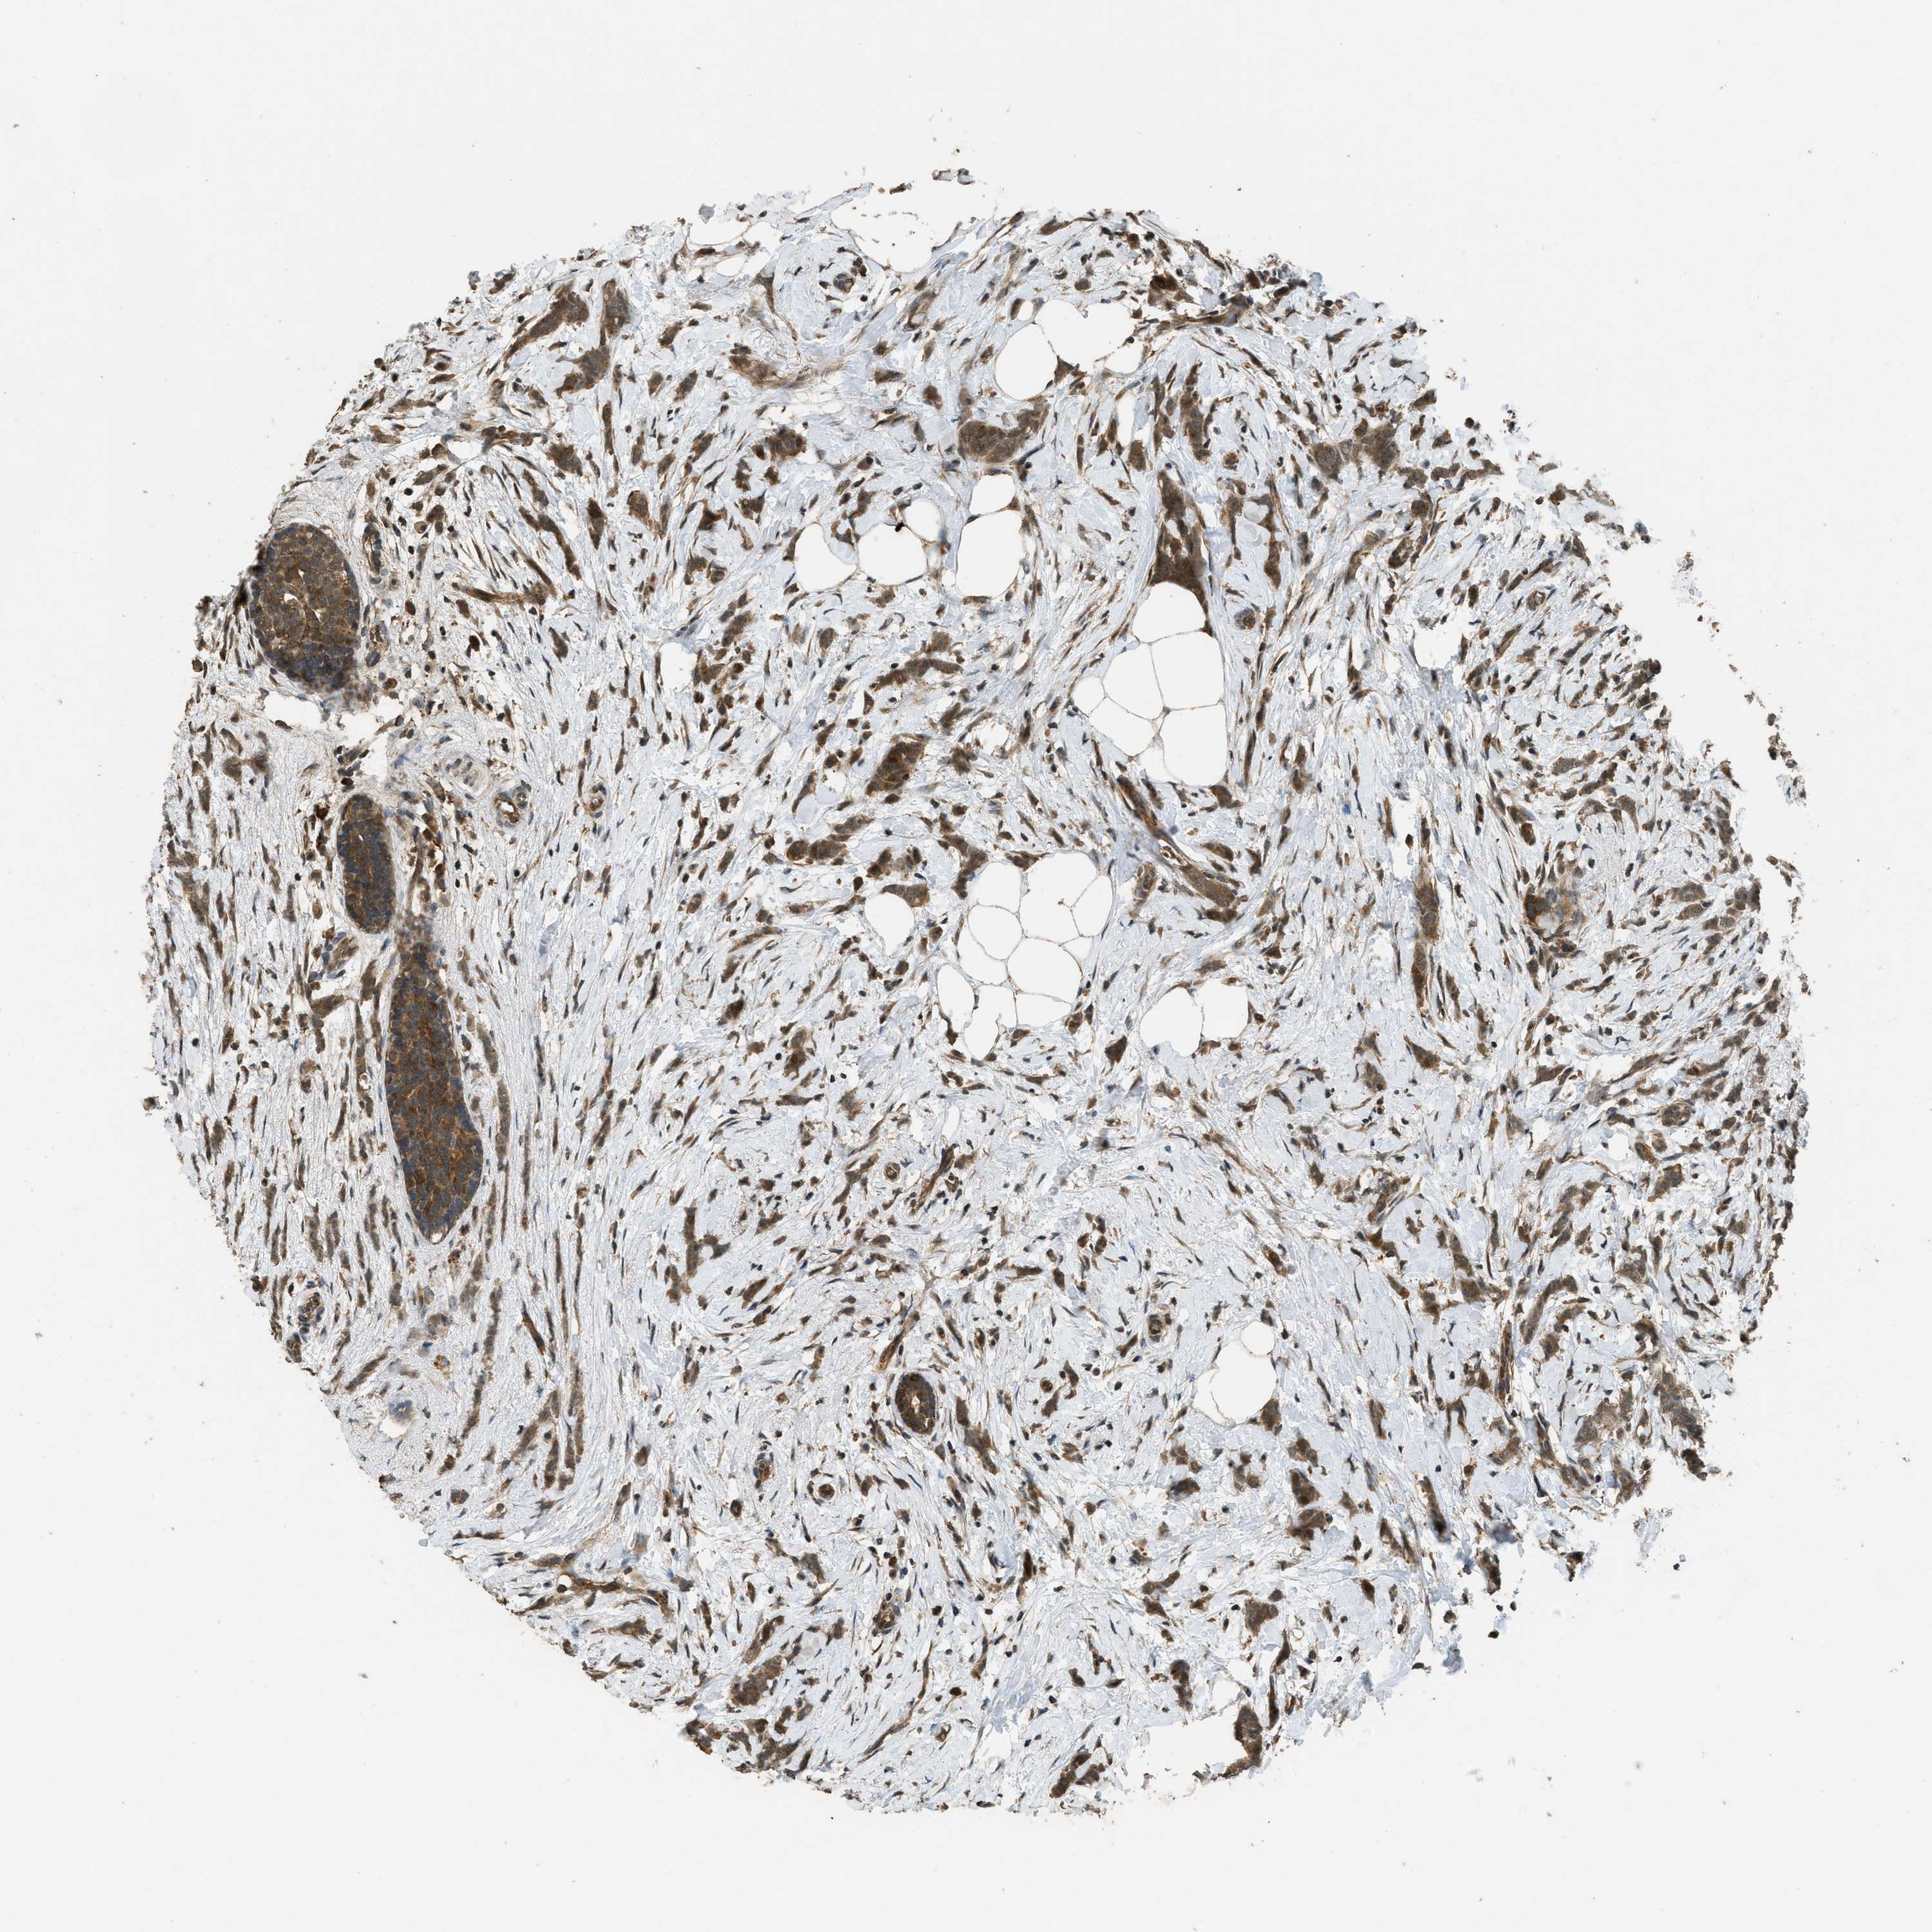

CANCER BREAST CANCER Show tissue menu

BRCA TCGA BRCA VALIDATION PROTEIN EXPRESSION